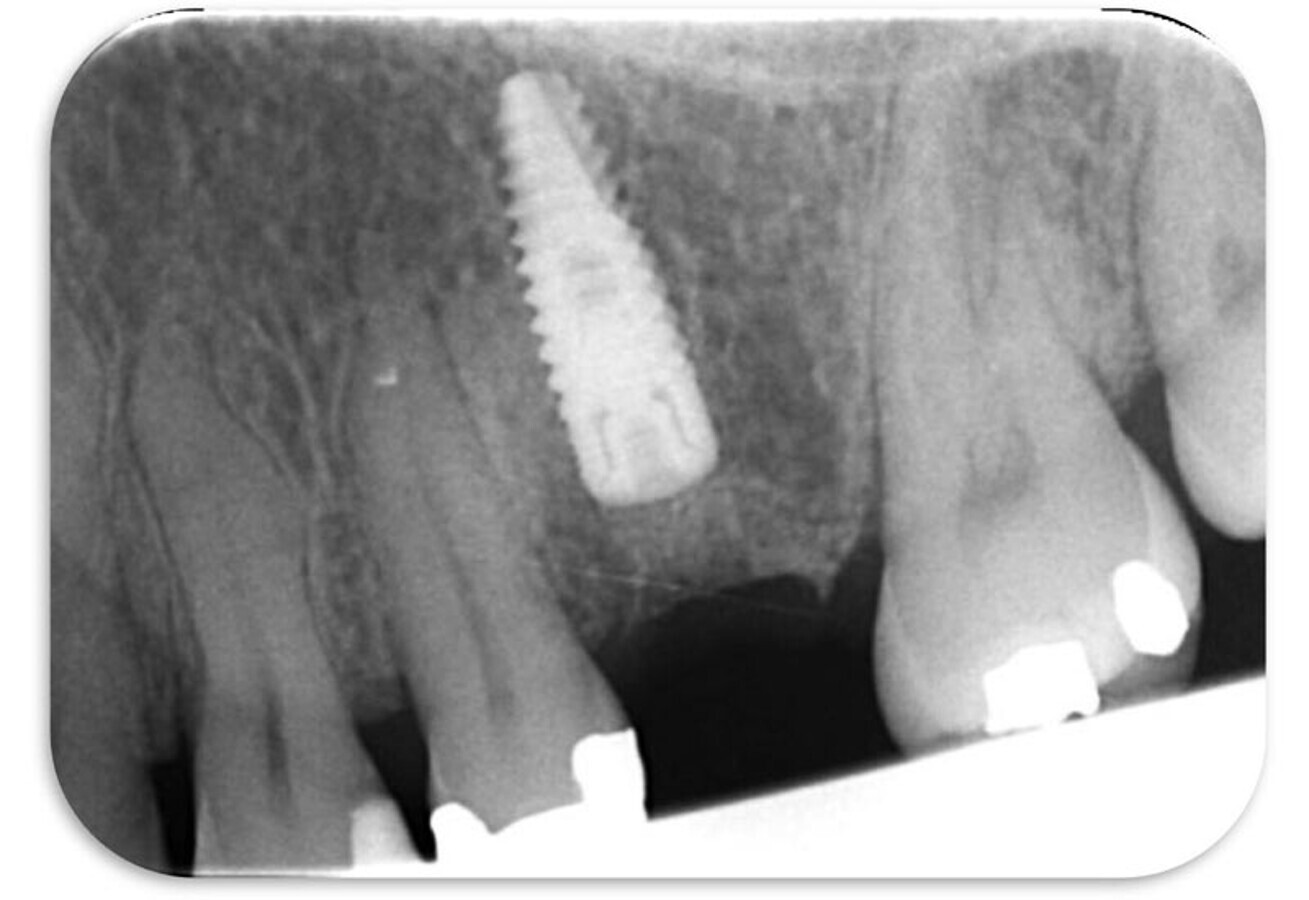

PA x-ray immediately post-op.

Looks spot on.